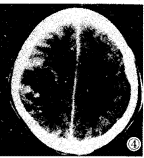

CT增强扫描:右颞顶叶病灶呈环状强化,环壁不均,左额叶病灶呈 均一强化,右侧侧脑室受压变扁,中线偏左(图3,4)。

图3,4 增强扫描右颞顶叶病灶呈环状强化,环壁不均;左额叶病灶呈均一强化